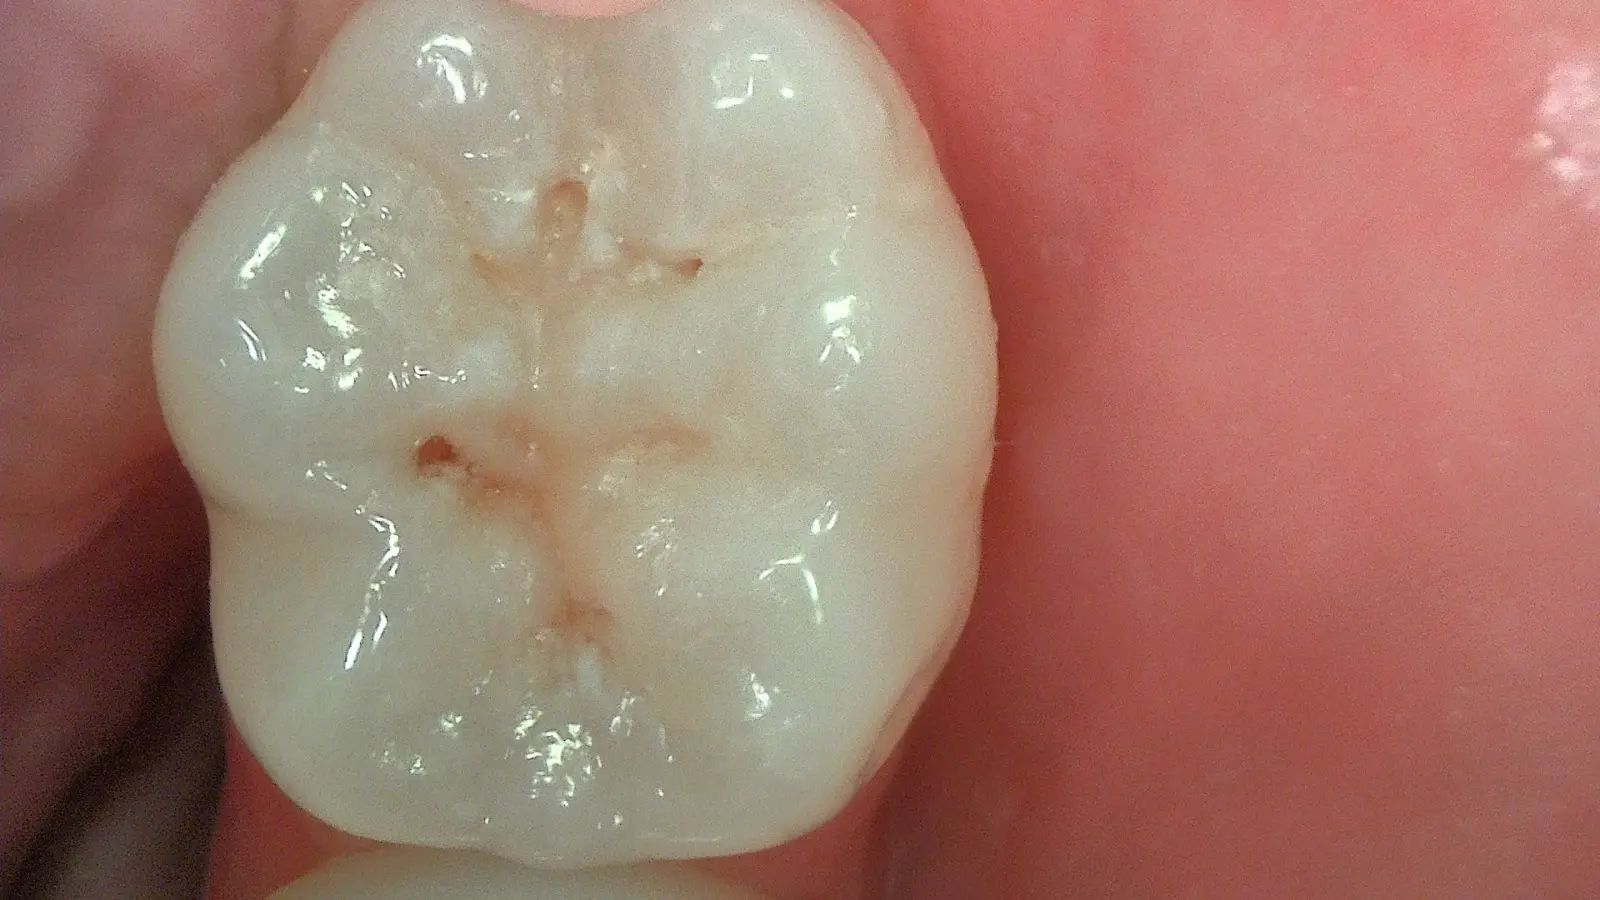

True-Colour Clinical Photography

Full HD white-light mode for standard clinical images — restorations, fractures, gingival condition and patient communication. Sharp, true colour at 1920×1080.

Experience the exceptional Full HD detail and fluorescence diagnostics in real patient cases — from early caries detection to minimally invasive restorations.